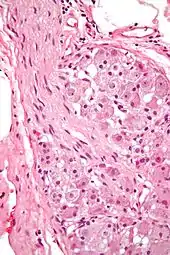

Ganglion cells within a ganglion. H&E stain.